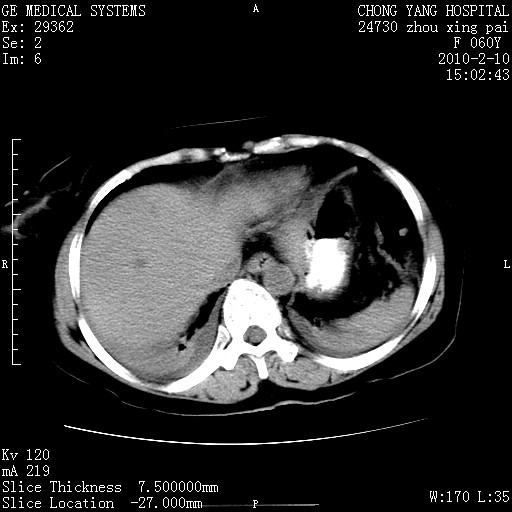

标题: CT24682:F60Y 腹痛 其它不详 [打印本页]

标题: CT24682:F60Y 腹痛 其它不详

胆总管末端梗阻!结石?肿瘤?建议增强!必要时行ercp!

胆总管末端梗阻!结石?胰腺影增粗,以胰腺头部为著,胰周看见渗出影,双侧胸腔积液,(胸膜反应)考虑胰腺炎。

1)胆总管末端梗阻,不排除结石所致可能。2)胰腺炎。3)慢性胆囊炎可能。4)左侧输尿管上段扩张。5)少量腹水。6)双侧少量胸腔积液,伴两下肺部分肺萎陷。

1)胆囊炎。2)胆源性胰腺炎。3)右肾周筋膜增厚,肾旁前间隙积液。4)左侧输尿管上段扩张。5)少量腹水。6)双侧少量胸腔积液,伴两下肺部分肺膨胀不全。

急性胰腺炎所致胆总管扩张!

1)胆总管末端梗阻。2)胰腺炎。3)慢性胆囊炎可能。4)左侧输尿管上段扩张。5)少量腹水。6)双侧少量胸腔积液,伴两下肺部分肺萎陷。